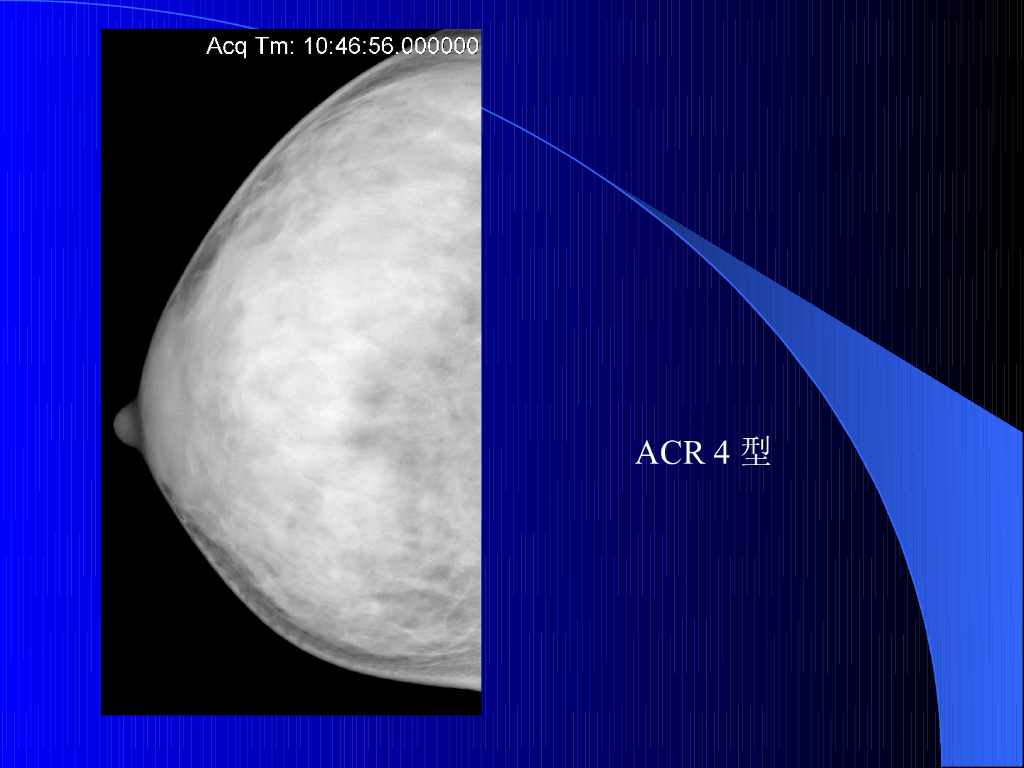

《放射诊断学》演示文稿-乳腺规范化诊疗及报告规范.pdf